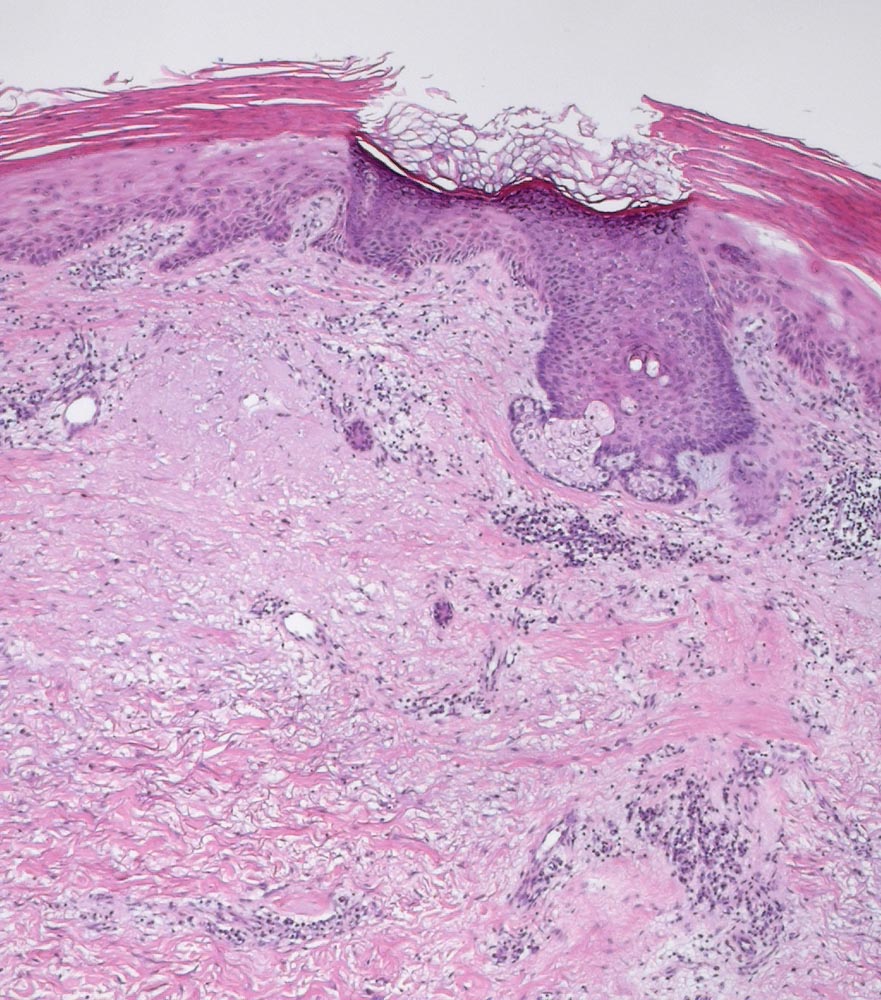

Morphologie:

Die Epidermis zeigt obligat dysplastische Veränderungen. Die Dysplasie kann sich auf das untereste Epitheldrittel beschränken (leichte Dysplasie) oder die gesamte Epithelbreite betreffen (=bowenoide aktinische Keratose bzw. Carcinoma in situ). In der Dermis findet sich als Zeichen der chronischen UV Schädigung der Haut immer eine ausgeprägte solare Elastose. Das histologische Bild ist abgesehen von diesen zwei obligaten Befunden sehr variabel. Dyskeratotische Zellen und Mitosen finden sich häufig. Charakteristisch ist auch das Vorliegen einer alternierenden Para- und Orthokeratose, die unterschiedlich stark ausgeprägt ist. Manchmal findet man eine Atrophie der Epidermis mit schmalem Stratum corneum oder umgekehrt eine massive Hyperkeratose wie beim Cornu cutaneum. Akrosyringium und innere Abschnitte der Haarfollikel sind von den dysplastischen Veränderungen ausgespart. Die Epidermis zeigt häufig eine unregelmäßige Hyperplasie mit in das Stratum papillare reichenden Knospen. Bei Ausdehnung der Dysplasie entlang von Haarfollikeln in die Tiefe, können sich bei zu oberflächlicher Abtragung der Läsion Lokalredzidive ausbilden.

Unterschieden werden mehrere histologische Subtypen der aktinischen Keratose: hypertropher, atropher, bowenoider, akantholytischer und pigmentierter Typ. Beim gleichen Patienten können unterschiedliche Subtypen vorkommen.

Der Übergang in ein frühinvasives malignes Plattenepithelkarzinom mit Metastasierungspotential ist histologisch nicht immer einfach erkennbar. Einzelzellinfiltrate, welche die Basalmembran durchbrochen haben, eine Stromadesmoplasie oder Zellnester innerhalb der retikulären Dermis werden als Merkmale für invasives Wachstum gewertet.